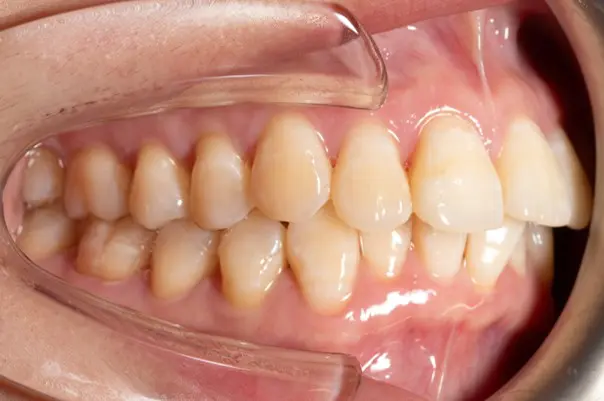

Before

After